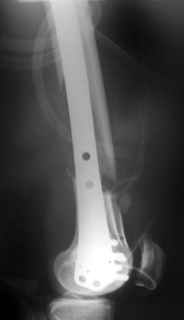

Отправитель: Alexander Chelnokov 31 Октябрь 2004, 20:44

Look what we would have done.